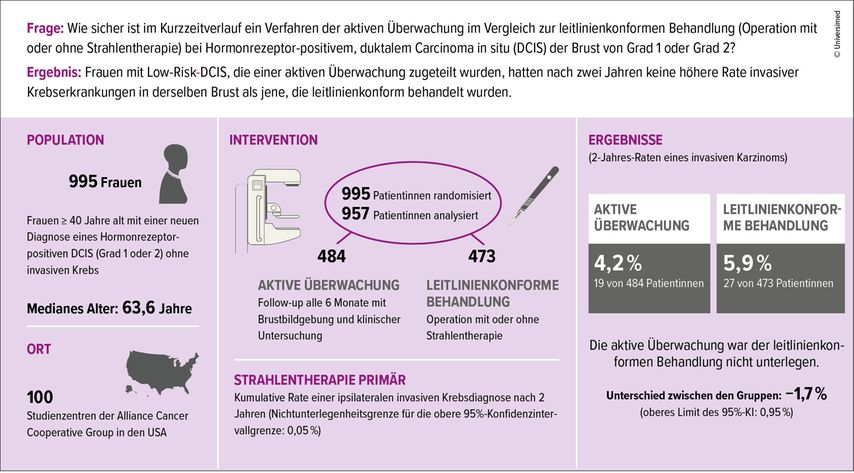

Schon vor zehn Jahren zeigte eine retrospektive Auswertung der US-amerikanischen «Surveillance, Epidemiology and End Results»(SEER)-Datenbank, dass bei Verzicht auf eine operative Behandlung bei «Low grade»-DCIS kein Nachteil hinsichtlich des Brustkrebs-spezifischen Gesamtüberlebens zu erkennen ist.5 Prospektive, randomisierte Studien haben bisher gefehlt, sodass in der Folge der genannten Publikation gleich drei grössere Studien initiiert wurden: der LOw RISk DCIS (LORIS) Trial, der LOw Risk DCIS(LORD)- und der Comparing an Operation to Monitoring, With or Without Endocrine Therapy for Low-Risk DCIS (COMET) Trial.6–8 Alle drei Studien berücksichtigen Patientinnen ab mindestens 40 Jahren mit «Non-high-grade»-DCIS. Zwei der Studien sind randomisiert, eine Studie (LORD) berücksichtigt die Präferenz der Patientinnen. Bisher publiziert wurden die Daten des COMET Trial, welcher untersucht, ob bei Patientinnen mit niedrigem Risiko ein «active monitoring» – also regelmässige Bildgebung und klinische Kontrollen – ebenso sicher ist wie die leitliniengerechte Therapie (Abb.2). In die Studie wurden knapp 1000 Frauen mit Hormonrezeptor-positivem, niedrig- bis mittelgradigem DCIS eingeschlossen. Die zentrale Fragestellung war: Lässt sich durch ein schonenderes Vorgehen eine ähnlich gute Sicherheit erreichen, ohne unnötige Therapien und deren Nebenwirkungen in Kauf zu nehmen? In der Gruppe mit «active monitoring» erhielten 19 Patientinnen (4,2%) im Verlauf die Diagnose eines invasiven Karzinoms, welches anschliessend standardgemäss therapiert wurde. In der Gruppe mit leitliniengerechtem Vorgehen erhielten 27 Patientinnen (5,9%) die Diagnose. In beiden Gruppen nahm die Mehrheit der Patientinnen (etwa 70%) eine endokrine Therapie ein.

Die Ergebnisse dieser Studie deuten eine neue Richtung im Umgang mit «Low grade»-DCIS an, sind jedoch keinesfalls überzubewerten. Denn zum einen ist der Beobachtungszeitraum mit gut zwei Jahren relativ kurz hinsichtlich des biologischen Verhaltens eines DCIS, zum anderen wurde mit über 70% Einnahme einer endokrinen Therapie eine hohe Compliance erreicht. Dass die konsequente endokrine Therapie protektiv hinsichtlich der Folgeinzidenz eines invasiven Karzinoms wirkt, konnte auch schon in früheren Studien gezeigt werden.9,10 Interessant ist, dass trotz einer gewissen Unsicherheit bei einem bioptisch nachgewiesenen DCIS die Patientinnen in beiden Gruppen keine Unterschiede hinsichtlich Besorgnis, Depression, Angst oder Lebensqualität aufwiesen. Auch wünschten sich mehr Studienteilnehmerinnen, in die Beobachtungsgruppe zu wechseln, als andersherum.6